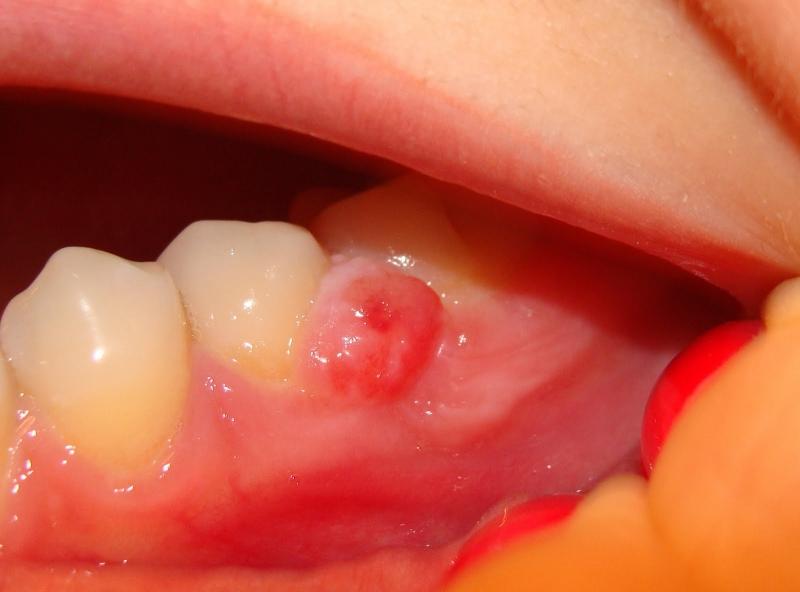

Основной причиной появления нароста на десне (см. фото) является попадание гнилостных бактерий в мягкие ткани. Существует множество факторов, способствующих образованию наростов, но можно выделить основные из них:

Если нарост представляет собой гнойную кисту, то он обычно сопровождается отеком и общим ухудшением состояния здоровья. В случае развития экзостоза – образования из костной ткани, его наличие на ранних стадиях определить довольно сложно, так как он не вызывает болезненных ощущений и может быть лишь нащупан языком.

На первичном осмотре врач обращает внимание на состояние десен, зубов и окружающих тканей. Важно провести визуальную оценку нароста: он может быть гладким или шероховатым, мягким или твердым, подвижным или фиксированным. Эти характеристики могут дать важные подсказки о природе образования.

Для более точной диагностики могут быть назначены дополнительные исследования. Рентгенография позволяет оценить состояние костной ткани и выявить возможные изменения, связанные с зубами или корнями. В некоторых случаях может потребоваться биопсия нароста, особенно если есть подозрение на злокачественное образование. Биопсия позволяет получить образец ткани для гистологического исследования, что помогает установить точный диагноз.